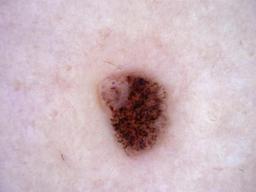

{

"age_approx": 35,

"anatom_site_general": "posterior torso",

"concomitant_biopsy": true,

"diagnosis_1": "Benign",

"diagnosis_2": "Benign melanocytic proliferations",

"diagnosis_3": "Nevus",

"diagnosis_confirm_type": "histopathology",

"image_type": "dermoscopic",

"lesion_id": "IL_1120917",

"melanocytic": true,

"sex": "male"

}